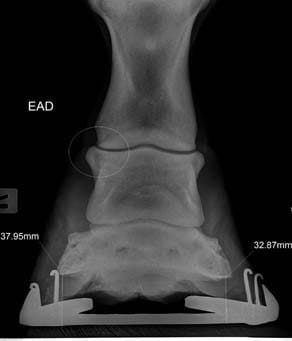

La radiología digital directa es una herramienta indispensable para el estudio v valoración en numerosas áreas de la atención veterinaria: valoración de cojeras, exámenes pre-compra, estudios radiológicos, diagnósticos más precisos en patologías, heridas, enfermedad…

Por eso nos mantenemos al día y nos renovamos con nuevos equipos de radiología digital directa que incorporan herramientas de diagnóstico y valoración con ventajas como:

- Herramientas de medidas más completas y potentes

- Medidas e imagen 3D para evaluación del pie equino

- Imagen hibrida. Diagnóstico v herrado